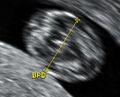

Gestational age is usually determined by the date of the woman's last menstrual period, and assuming ovulation occurred on day fourteen of the menstrual cycle. Sometimes a woman may be uncertain of the date of her last menstrual period, or there may be reason to suspect ovulation occurred significantly earlier or later than the fourteenth day of her cycle. Ultrasound scans offer an alternative method of estimating gestational age. The most accurate measurement for dating is the crown-rump length of the fetus, which can be done between 7 and 13 weeks of gestation. After 13 weeks of gestation, the fetal age may be estimated using the biparietal diameter (the transverse diameter of the head, across the two parietal bones), the head circumference, the length of the femur, the crown-heel length (head to heel), and other fetal parameters.[citation needed] Dating is more accurate when done earlier in the pregnancy; if a later scan gives a different estimate of gestational age, the estimated age is not normally changed but rather it is assumed the fetus is not growing at the expected rate.[5]